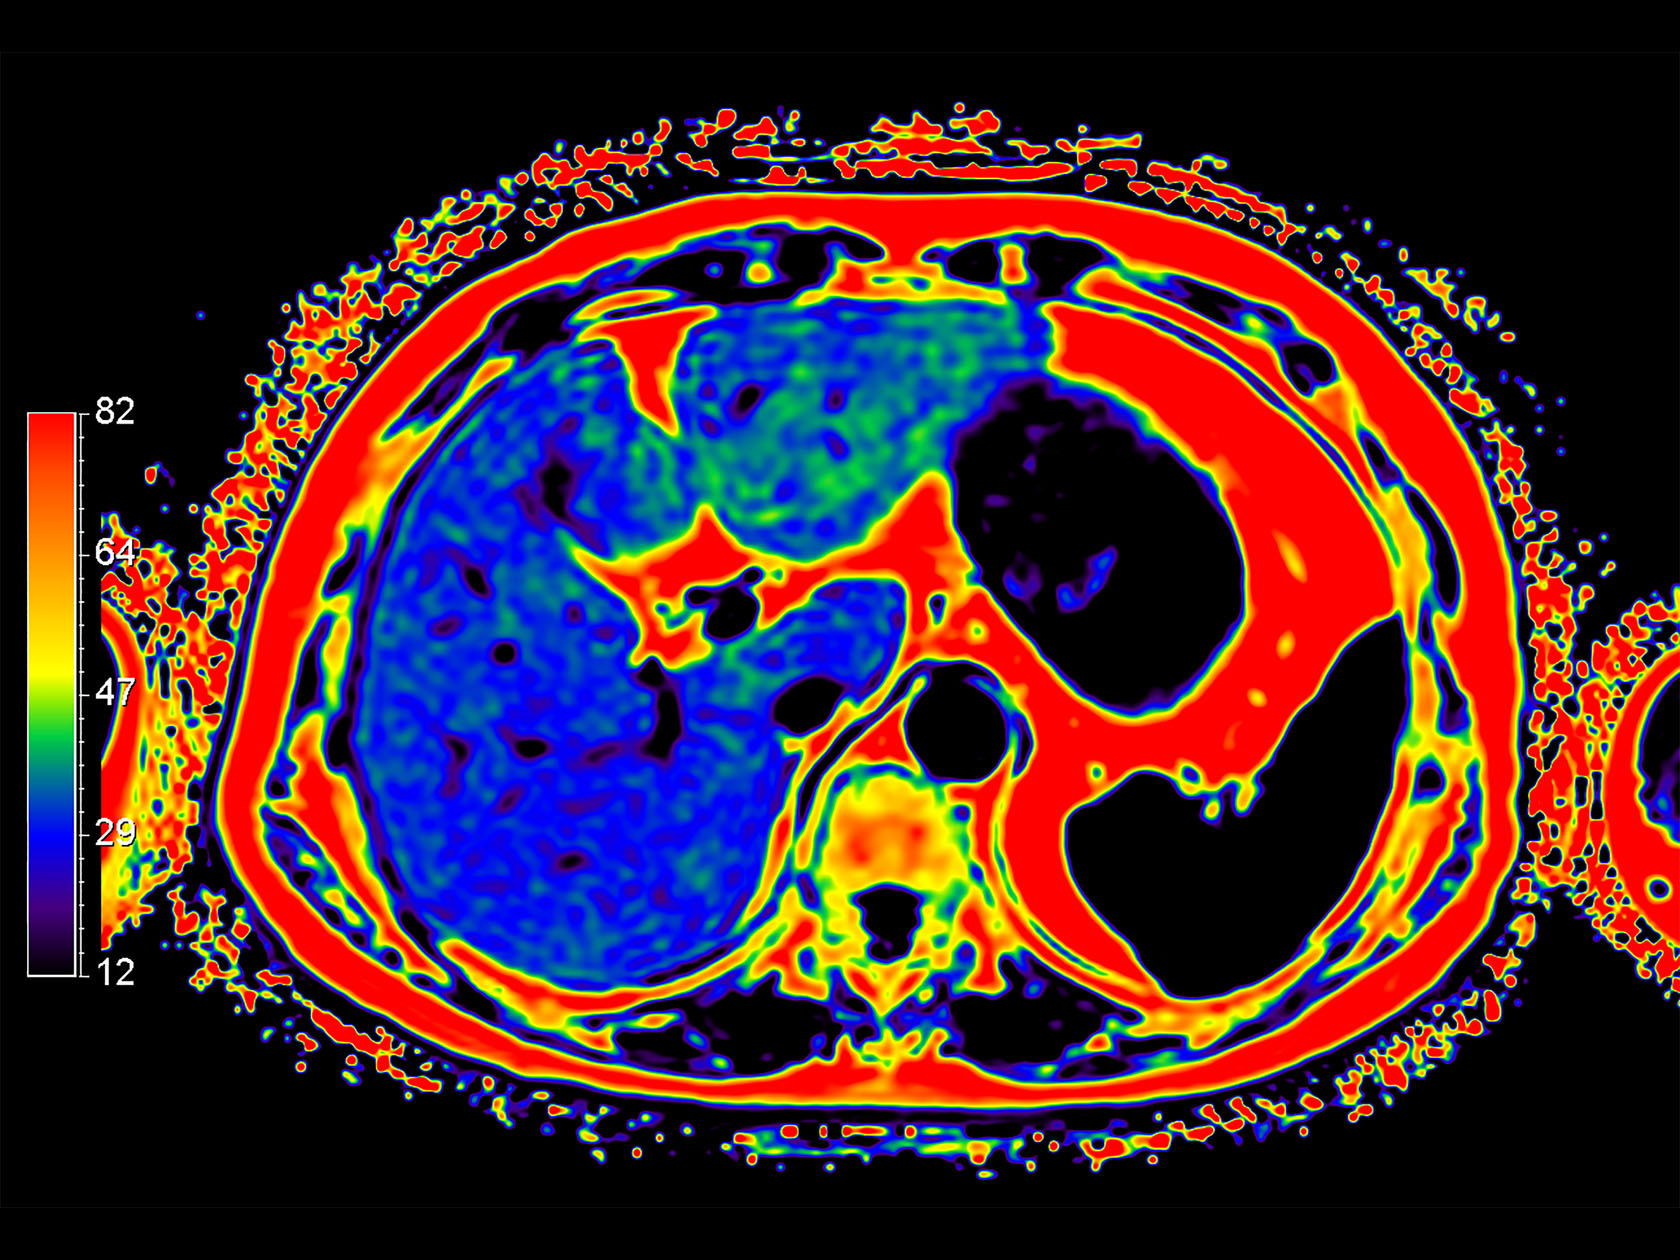

Diffusion (ADC)